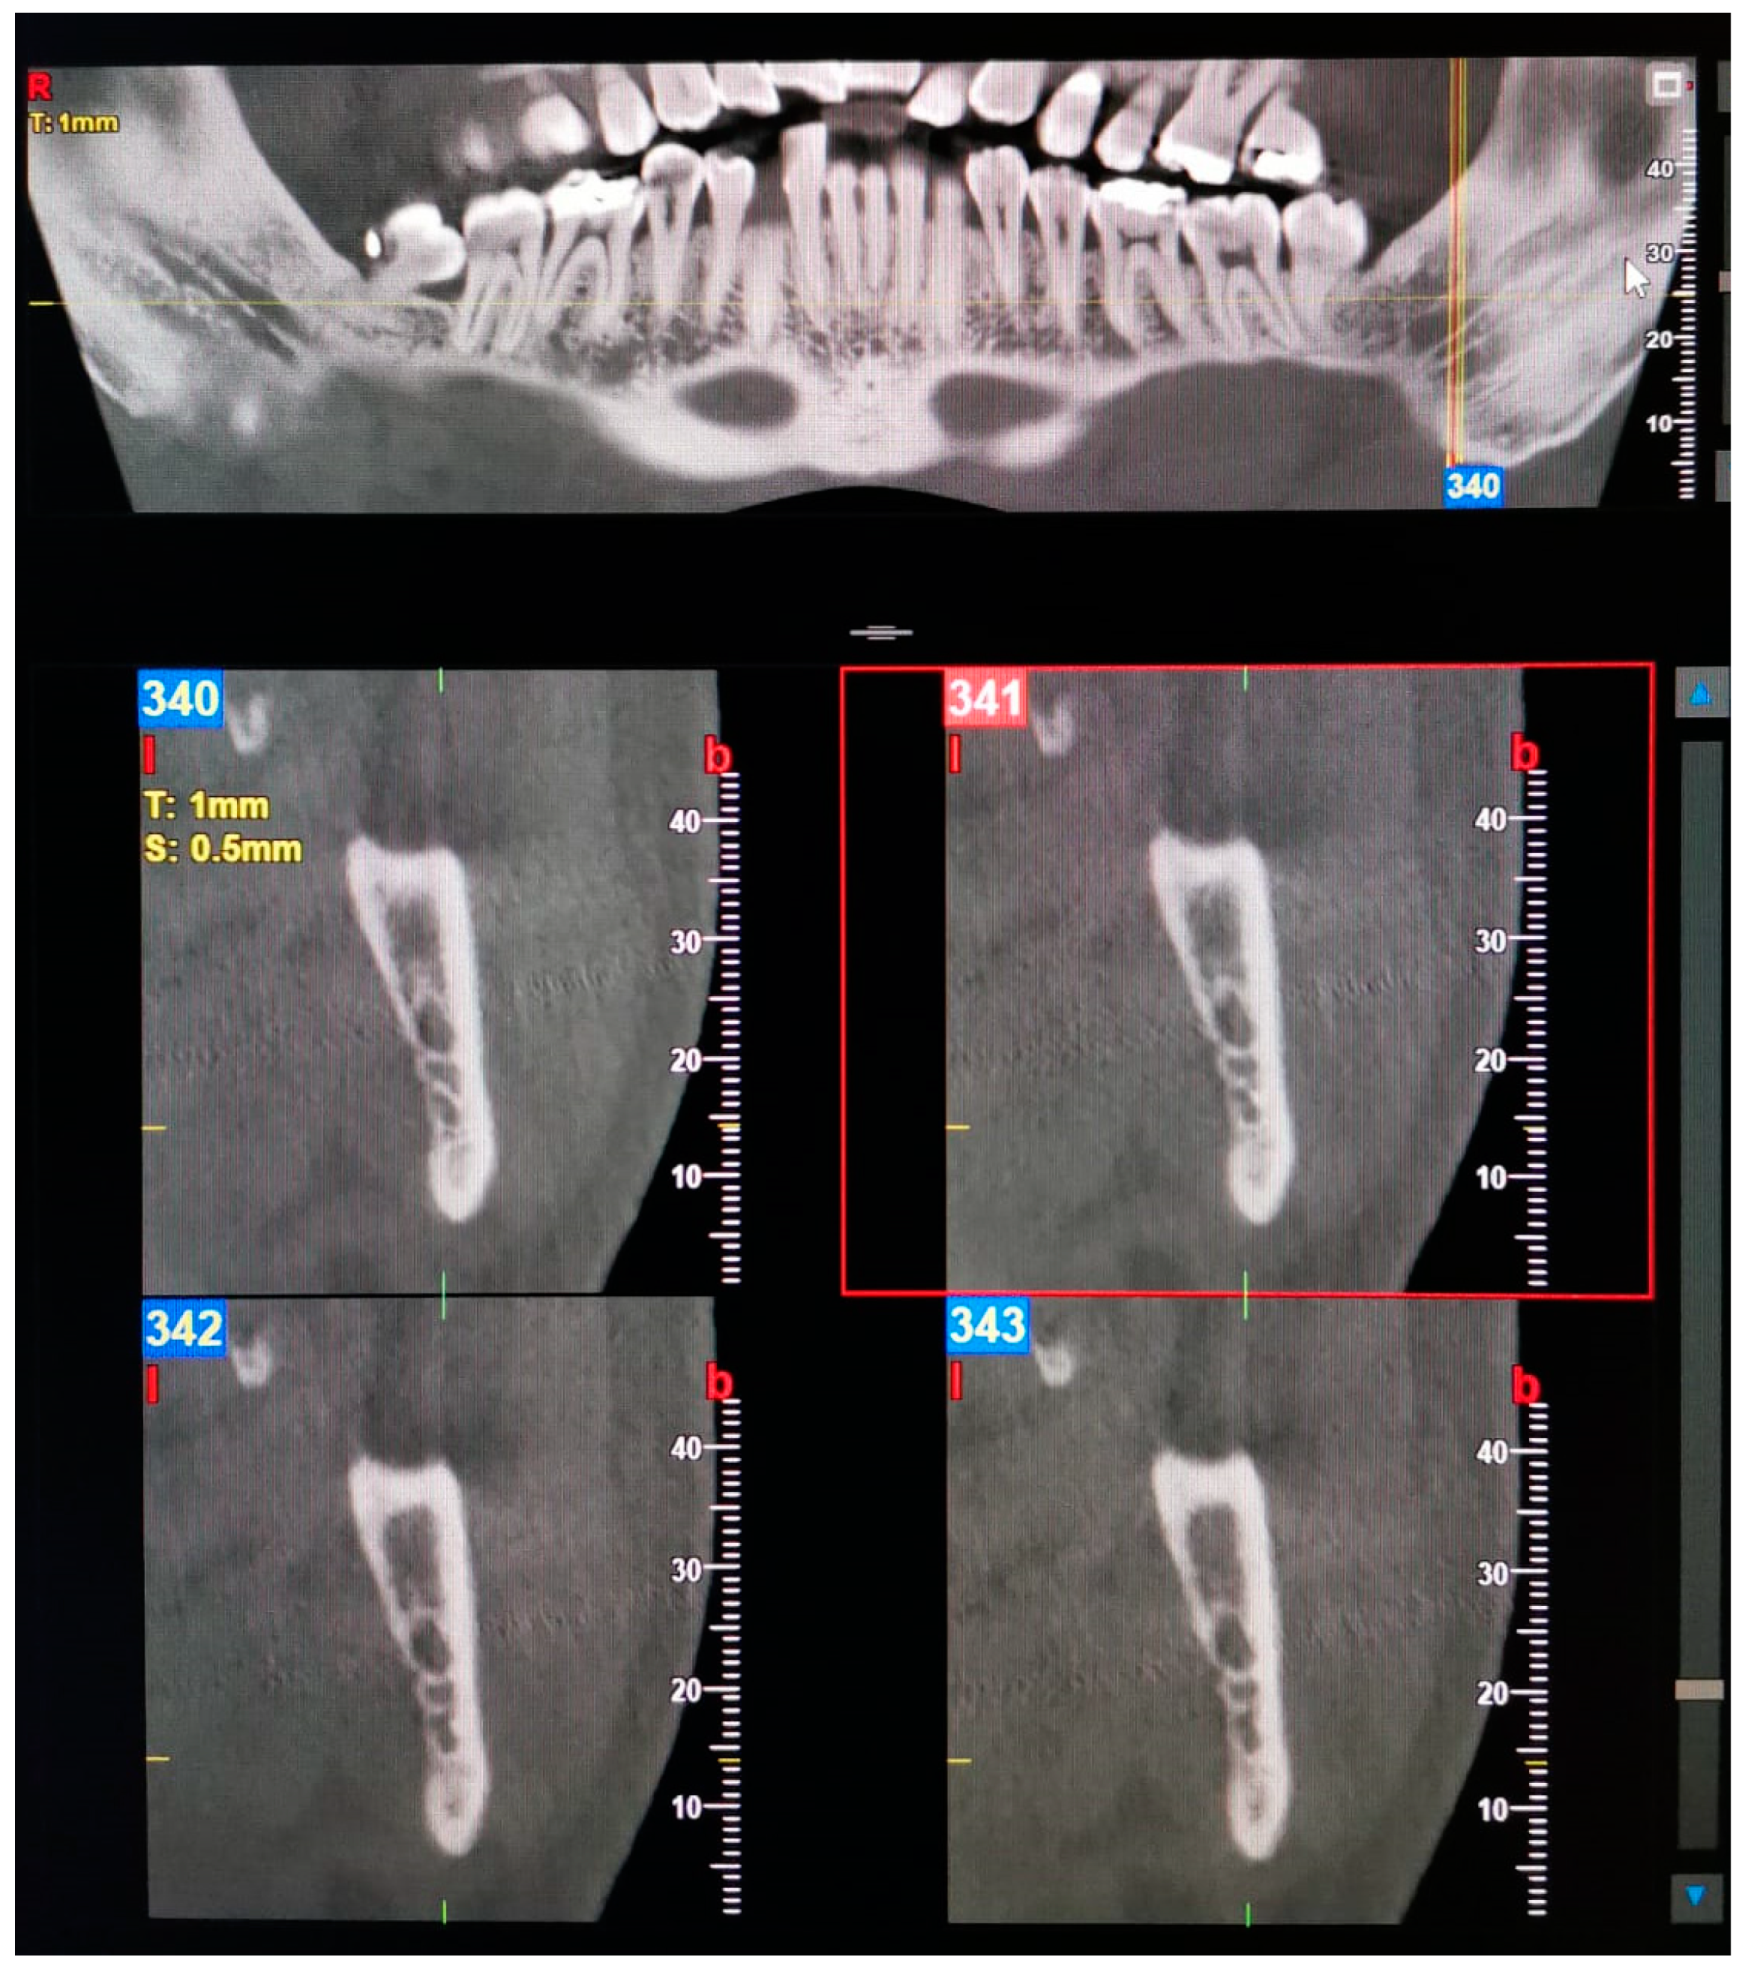

| 1—Retromolar | The retromolar canal, which bifurcates from the mandibular canal in the mandibular ramus region, courses forward, reaching the retromolar region. |

| 2—Dental | The dental canal, which bifurcates from the mandibular canal in the mandibular ramus region, courses forward, reaching the roots of the molars. |